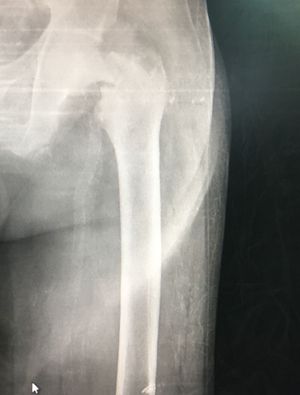

Hip x Ray

What is diagnosis??

Femoral head fracture

Type 4 femoral head fracture the most severe fracture of femoral head